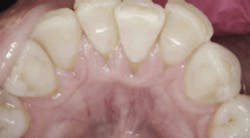

On July 7, 2016, when the patient returned, bleeding was reduced from 101 sites to seven sites, and deep pockets decreased from 37% to just 2%. The patient was then asked to incorporate the trays into her regular home care, using them once a day for 15 minutes.

Taken after probing on July 7, 2016. Image courtesy of Perfect Teeth–Frank Lloyd Wright.